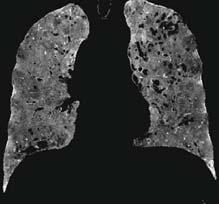

The world’s first singlesource photon-counting CT

siemens-healthineers.ca/naeotom-alpha-prime

Part of the NAEOTOM Alpha class family, NAEOTOM Alpha.Prime is the fastest, highest-resolution single-source CT in our portfolio and is now available in Canada. It expands access to Quantum Technology while preserving the image quality and diagnostic confidence that define the NAEOTOM Alpha class. NAEOTOM Alpha. Prime delivers ultra-high resolution imaging and spectral information in every scan, making photon-counting CT more accessible than ever.

Courtesy of Diagnostikum Graz, Austria The products/features (mentioned herein) are not commercially available in all countries.